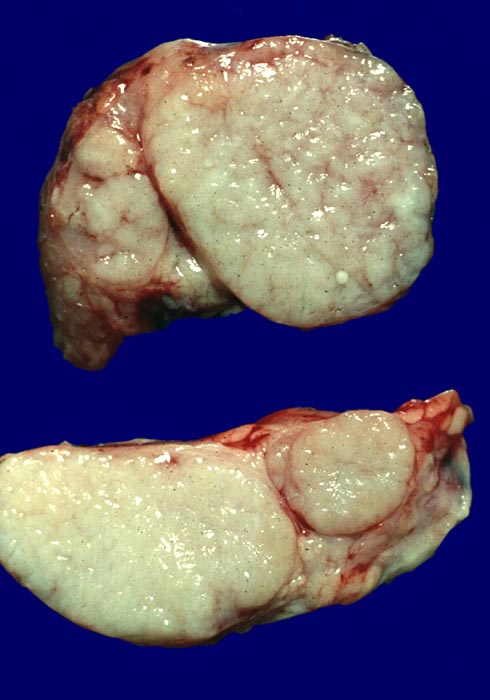

PathoPic ID 3851 - Lymphknotensarkoidose

Lymphknotensarkoidose

Lymphknoten

Lymphatische Gewebe, KM, Milz

Anstelle von gräulichem Lymphknotengewebe sieht man auf der Schnittfläche dieses Lymphknotens miteinander konfluierende gelbweisse Knoten (Granulome).

Makroskopie